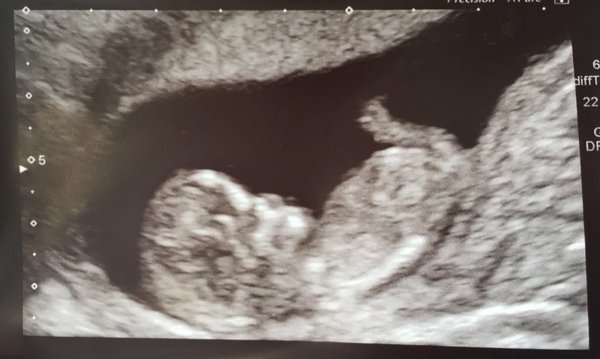

I had a scan today and can’t believe how human the baby looks now!

@Elizabeth134 lovely scan! Baby looks so clear on the pic!

@Angelmiracle baby looks so comfy in there, very cute!

@SquirtlesMumAgain really glad all went with with your scan, lovely pic!

@Elizabeth134 lovely scan! There are no legs visible in my pics, so it's quite fun seeing them in other people's. Gives a bit more of an idea of what they really look like.

Lovely scan @Elizabeth134

@Elizabeth134 lovely whole baby scan pic glad all is well.